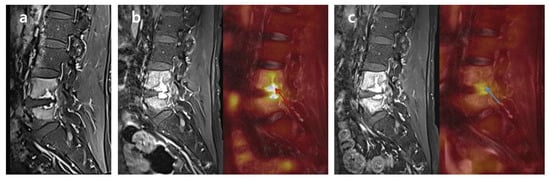

2.3. FDG-PET/MRI and Image Analysis